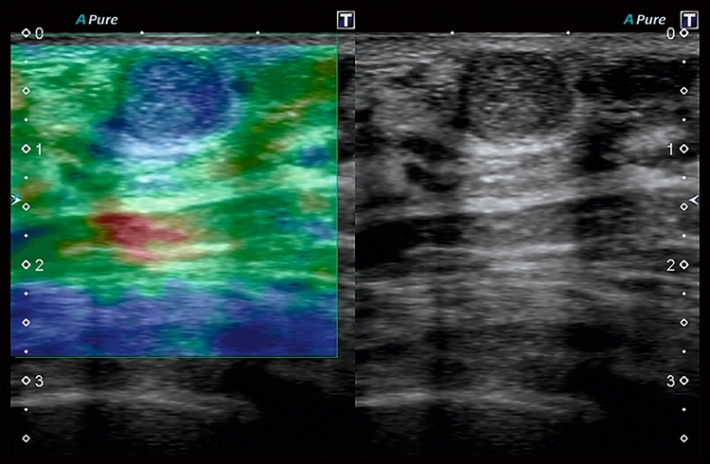

Изображения